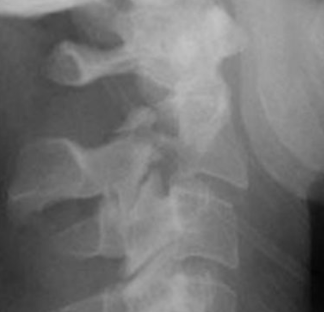

What type of fracture is this?

Compression

What is a compression fracture?

Vertebral fracture displays as decreased vertical dimension of anterior vertebral body

Lower t-spine usually